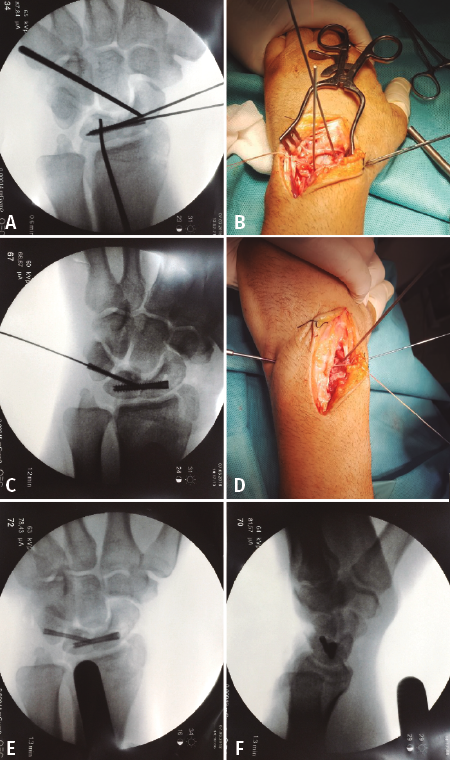

Se intervino al paciente bajo anestesia regional e isquemia. Se realizó abordaje dorsal de la muñeca. Disección por planos, piel y tejido celular subcutáneo. Apertura de la 3.ª y la 4.ª correderas, separándose los tendones hacia radial y cubital, respectivamente, exponiendo el retináculo extensor y la cápsula articular de la muñeca.

Cauterización de la rama interósea posterior, rama sensitiva terminal del nervio radial, localizada en el suelo de la 4.ª corredera. Apertura de la cápsula articular longitudinalmente.

Bajo visión directa se corroboró la existencia de la lesión sospechada en las radiografías y TC prequirúrgicas, y una lesión no reparable del ligamento escafolunar. El hueso grande articulaba directamente con el radio, ocupando la fosa semilunar del radio. A continuación, se redujo el carpo, mediante tracción y flexión palmar forzada, acompañado de una presión directa del semilunar. Cruentación de todo el cartílago de las superficies articulares entre el semilunar y el escafoides, hasta conseguir exponer el hueso subcondral. A continuación, para ayudar en la manipulación y reducción de ambos huesos se colocaron 2 agujas de Kirschner a modo de joystick. Una vez reducidos, se realizó la osteosíntesis mediante tornillo Acutrak Mini®(Figuras 3A y 3B). En un segundo tiempo se retiró el cartílago articular de las superficies articulares entre el semilunar y piramidal. Se redujo con ayuda de una aguja de Kirschner y osteosíntesis con un Acutrak Micro®(Figuras 3C, 3D, 3E y 3F). En último lugar, se realizó una plicatura y cierre capsular mediante un implante Minilok®; se reforzó con puntos simples. Cierre de la 3.ª y la 4.ª correderas. Férula con inmovilización del primer dedo durante 8 semanas. Extracción del material de osteosíntesis a las 8 semanas. El objetivo de esta técnica (reduction and association of the scaphoid and lunate –RASL–) es conseguir una pseudoartrosis, cuya falta de consolidación consigue mejor control del dolor, amplitud de movimiento y fuerza de agarre que con una artrodesis exitosa(2,3).

Figura 3. A y B: osteosíntesis del semilunar y escafoides con Acutrack Mini®; C y D: osteosíntesis del semilunar y escafoides con Acutrack Micro®; E y F: resultado postoperatorio inmediato.